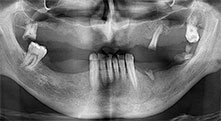

Professor Dr. Dr. Emanuel Bratu, maxillofacial surgeon, oral surgeon and prostheticist, is head of the implantology departments at two Romanian universities. He runs a renowned private hospital in Timisoara and is an internationally known researcher. In the interview Bratu explains why he considers that the W&H Piezomed piezosurgical device, and particularly two patented saws, have become essential for bone surgery.

Professor Bratu, what is your experience with the new B6/B7 saws for the W&H Piezomed?

Bratu: These saws feel completely different from previously available piezosurgical instruments. They are really astoundingly effective. We noticed immediately that the Piezomed B6/B7 work much faster than other saws. They are also easier to guide in bone, particularly in thick bone layers.

According to W&H this is due to the high power output of the surgical unit combined with the very fine teeth and the small diameter of the saw blades of only 0.25 mm.

For what indications do you use the saws?

Bratu: We routinely use the instruments for harvesting bone blocks and splitting alveolar ridges. We also use the Piezomed B6/B7 for osteotomy of impacted teeth and removing failed implants. All indications that require deep, clean cuts.